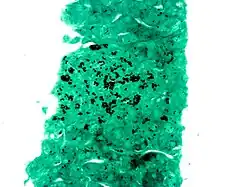

La tinción argéntica es el uso de plata (en latín, Argentum) para modificar selectivamente el color o la apariencia de un objeto. Es una técnica frecuente de tinción en histología donde se utiliza para revelar detalles extremadamente finos.

La tinción argéntica se utiliza en microscopía óptica. Las partículas de plata metálica se depositan en las fibras de reticulina sensibilizadas y son fácilmente observables en los preparados microscópicos.

La tinción argéntica tiene utilidad ayudando a revelar las fibras reticulares.[1]